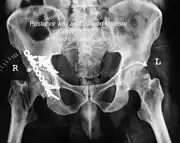

Posterior wall fracture fixed with screws and plate